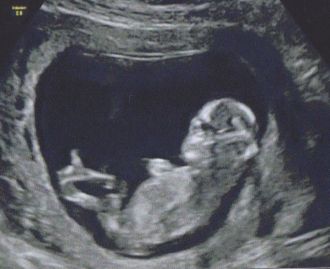

Echographie Ier trimestre

Les annonces se sont multipliées, comme indiqué ci-dessous, après l'échographie du premier trimestre, réalisée le 10 novembre.

Cette première échographie était très attendue par nous deux, ce sont toujours des moments magiques!

Bilan de l'écho: tout va bien!!!!!

Le bébé se développe tout bien comme il faut et bougeait pas mal!!!! Il a tout ce qu'il faut où il faut, bref, RAS de spécial pour le moment, ouf! C'est l'un des rares moments où l'on aime la normalité!!! LOL!

Même si on a tout vu, l'écho n'a malheureusement pas duré longtemps et nous en gardons un souvenir un peu mitigé (un vrai sentiment de "vite fait" et quelques clichés papiers pas terribles)... il faut dire que, pour Rémi, l'échographe était vraiment au top mais elle n'avais déjà plus de dispo la semaine où il nous fallait la faire donc pas le choix....

Malgré tout, nous en sommes sortis rassurés, avec le son de son petit cœur qui raisonnait dans les nôtres. Cette écoute est toujours un moment très fort pour Anthony qui, comme il le dit lui même "lui met toujours une claque"; d'ailleurs, je l'ai entendu "sourire" (oui, oui, c'est possible!!!! LOL! Il a aussi émis un son en même temps, ça aide!) au moment de la découverte de ce doux son!

Et, nous avons aussi un petit bonus.... ce sera à confirmer lors de l'écho de janvier (le 22, avec la super échographe!)) mais il se pourrait bien que bébé 2 soit une petite puce!!!!!!!!!! En effet, nous l'avons tous bien vu, le tubercule génital qui peut permettre ces suppositions était bien parallèle à la colonne vertébrale alors qu'à ce même stade, il était déjà bien vers le haut pour Rémi!!! Comme ce n'est pas une science exacte, nous attendons tout de même la confirmation avec joie et impatience! Mais, de toutes façons, qu'importe, un deuxième petit mec nous irait très bien aussi!

Bref, nous attendons notre bébé et il sera parfait!!!!!!!!!

PS: lors de cette écho, effectuée à 12SA tout pile, bébé mesurait 55mm de la tête aux fesses! ^^